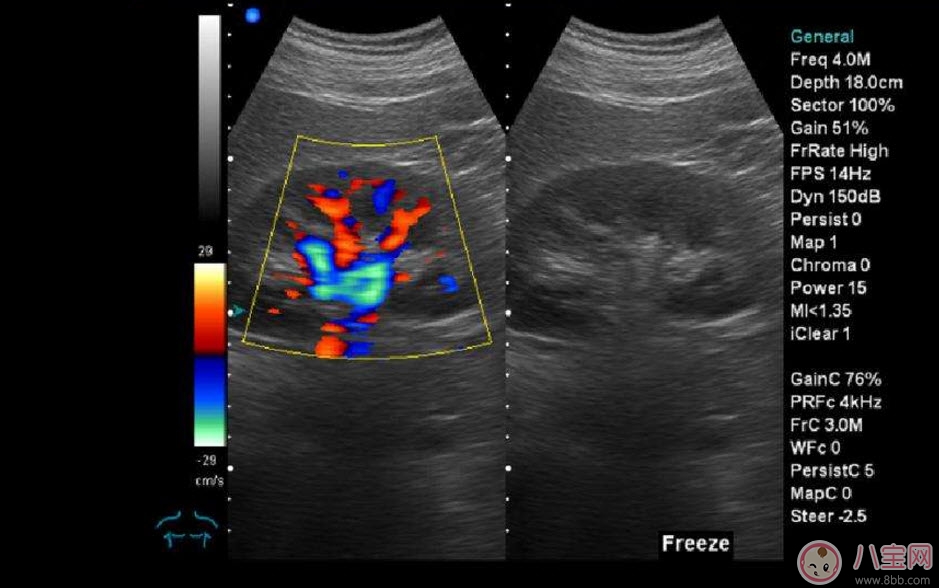

??B超也稱為二維超聲,分為黑白的和彩色的兩種。 彩超其實還是黑白的,彩超簡單的說就是高清晰度的黑白B超再加上彩色多普勒,既具有二維超聲結(jié)構(gòu)圖像的優(yōu)點,又提供了血流動力學(xué)的豐富信息。彩超的分辨率會比一般黑白B超高一些,所以在需要做比較細致的檢查的時候,更多的醫(yī)生愿意通過彩超來檢查。例如,因為彩超能用彩色標注血流,所以當(dāng)臍帶繞頸的時候就會看見寶寶的脖子上呈U形或者W形的血流,對是否臍帶繞頸也就一目了然了。目前用于產(chǎn)檢的超聲波一般都是二維的。

除了能觀察到通過B超觀察到的一切外,彩超能夠直觀成像,顯示更清晰,結(jié)果也更快速,可發(fā)現(xiàn)異常血流,為診斷胎兒先天性心臟缺陷提供了診斷依據(jù)。價格要比B超貴,大概在150元左右(會根據(jù)各地具體情況的不同而上下浮動)。二維彩超適用于整個孕期,特別是臨產(chǎn)前。二維彩超的圖像也并非就是彩色的,而是用彩色標注心臟、血流等指標,其實就是高清晰度的黑白B超再加上彩色多普勒。觀測到的圖像以紅藍兩色血流方向為主,面向探頭的呈現(xiàn)紅色,反之為藍色。這種技術(shù)能夠觀測到胎兒的血液流動情況,有利于及時發(fā)現(xiàn)胎兒的異常。比如,發(fā)現(xiàn)胎兒頸部有血流環(huán),則意味著發(fā)生了可導(dǎo)致窒息死亡的臍帶繞頸。